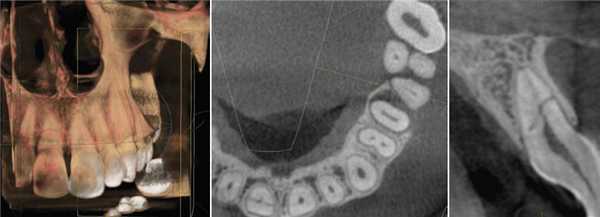

7. Компьютерная томография (КТ).

Метод позволяет получить изображение не только костных структур челюстно-лицевой области, но и мягких тканей, включая кожу, подкожную жировую клетчатку, мышцы, крупные нервы, сосуды и лимфатические узлы.

Компьютерная томография широко используется при распознавании заболеваний лицевого черепа и зубочелюстной системы: патологии височно-нижнечелюстных суставов, врожденных и приобретенных деформаций, переломов, опухолей, кист, системных заболеваний, патологии слюнных желез, болезней носо- и ротоглотки.

Метод позволяет разрешить диагностические затруднения, особенно при распространении процесса в крылонебную и подвисочную ямки, глазницу, клетки решетчатого лабиринта.

С помощью КТ хорошо распознаются внутричерепные осложнения острых синуситов (эпидуральные и субдуральные абсцессы), вовлечение в воспалительный процесс клетчатки глазницы, внутричерепные гематомы при травмах челюстно-лицевой области.

Компьютерная томография позволяет точно определить локализацию поражений, провести дифференциальную диагностику заболеваний, планирование оперативных вмешательств и лучевой терапии.

Компьютерная томография зубов

Компьютерная томография зубов (КТ) - это относительно новый для стоматологии метод рентгенологического обследования зубов, челюстей и мягких тканей лица, который позволяет получить трехмерный 3D снимок зубов пациента. Трехмерный снимок на экране компьютера возникает в результате объединения большого количества послойных двухмерных снимков в единое целое, что становится возможным благодаря сложному программному обеспечению.

Этот метод обычно значительно информативней традиционной двухмерной плоской рентгенографии зубов, но это относится только к снимкам с высоким разрешением. Аппараты компьютерной томографии стоят очень дорого, клиники стараются эксплуатировать их до последнего, и поэтому очень часто приходится видеть и малоинформативные снимки с небольшим разрешением.

Если снимок КТ сделан в хорошем разрешении, то в сравнении с двухмерными традиционными рентгеновскими снимками - трехмерная цифровая компьютерная томография безусловно позволяет во много раз повысить качество диагностики, снизить риск постановки неправильного диагноза. Все это обеспечивается более высоким разрешением таких снимков, а также возможностью послойно исследовать объект на экране компьютера.

Эта новая возможность получения изображения в трехмерном измерении значительно повысила уровень терапии в стоматологии по всему миру. КЛКТ постепенно становится золотым стандартом в обеспечении точной постановки диагноза, составления плана лечения и проведения лечения. Конусно-лучевая техника на настоящий момент имеет множество областей применения в стоматологии, это и планирование имплантации, хирургическая оценка патологии, оценка ВНЧС, выявление роста и развития для ортодонтических целей, дооперативная, оперативная и послеоперативная оценка при краниофациальной травме, краниофациальная реконструкция и хирургия полости рта. Вдобавок, КЛКТ используется для выявления точной локализации инородного тела в мягких тканях, выявлении расщепленной губы и неба, а также глубины кариозного поражения. КЛКТ становится типичным инструментом в деятельности хирурга, особенно имплантолога.

Конусно-лучевая компьютерная томография

КЛКТ используется в стоматологии начиная с 1981 года. В отличие от обычного КТ, которое создает изображение на разных слоях, КЛКТ создает изображение в 3D пикселях называемых воксель. Так как эти воксели являются изотропичными, объект тщательно измеряется в различных направлениях. Это позволяет визуализировать геометрически неискаженное изображение челюстно-лицевой области, которое возможно просматривать при разных углах. Вдобавок для обеспечения высокого разрешения изображения, КЛКТ доступно для просмотра с разных точек (FOV) для применения в различных ситуациях. В эндодонтии аппарат с ограниченным FOV обычно является достаточным. Обычно, чем меньше объем скана, чем выше пространственное разрешение изображения. Так как ранний симптом периапикальной патологии это прерывистость твердой пластинки и расширение периодонтальной щели, оптимальным разрешением при получении КЛКТ изображения, применяемом в эндодонтии, не должно превышать 200 нм - средняя ширина периодонтального пространства. 3D Accuitomo (K Morita, Corporation, Kyoto, Japan) - первая из малых FOV систем - обеспечивает разрешение в 0,125 мм. Orthophos XG3D (Sirons Germany) также обеспечивает получение FOV 5*5 специально для эндодонтических целей.

КЛКТ дает гораздо меньшую радиационную нагрузку, чем обычный КТ. Экспозиционная доза при проведении цифровой радиографии сравнима с получение обычных диагностических панорамных или прицельных снимков. Получение изображений для всей полости рта облучает примерно на 150 usv. Очевидно, что скан КЛКТ одного зуба с высоким разрешением, примененный в диагностическом процессе, заменяет 3 прицельных снимка. Трудно представить, что экспозиционная доза может быть более важным моментом, чем получение КЛКТ в благоразумной манере для получения информации, которая просто недоступно при работе с другими приборами.